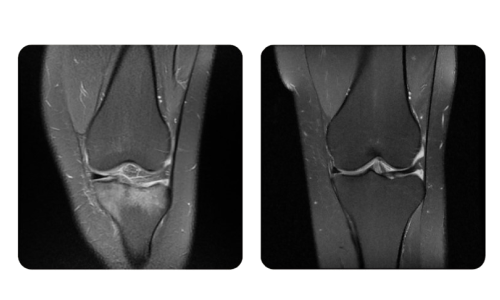

I progressi dei nostri pazienti, misurati prima e dopo la terapia iperbarica, riflettono l'efficacia e l'impatto positivo del trattamento. Scopri i risultati documentati della terapia iperbarica presso la clinica Hyperbarium Oradea, basati su valutazioni cliniche e dati oggettivi che evidenziano miglioramenti significativi in diverse condizioni.